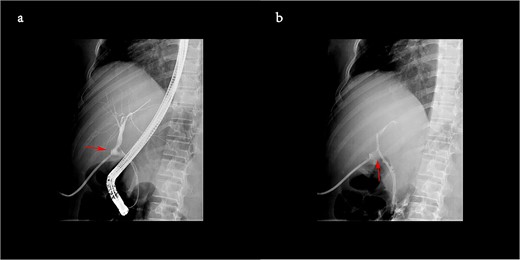

Despite the absence of obstruction on the T-tube cholangiography performed at the local hospital, we recommended ERCP. The biliary tract contrast during the operation revealed a slight distortion of the common bile duct (shown in Fig. 2), and a plastic biliary stent was placed to mitigate the distortion. The T-tube was subsequently removed, as her jaundice resolved rapidly following the procedure (bilirubin levels dropped from 382 to 159 μmol/L within 4 days).

The biliary tract contrast during ERCP showed a slight distortion of duct (a), and one plastic biliary stent was placed to mitigate the distortion (b).

Finally, the patient was diagnosed with obstructive jaundice due to the distortion of the common bile duct (CBD) caused by the T-tube. And the plastic biliary stent was scheduled for removal 3 months later.